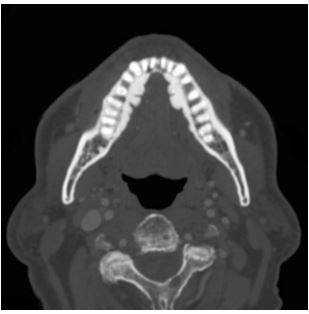

КТ, биопсия, другие методы диагностики

Чтобы получить представление о локации и распространении новообразования, делают компьютерную томографию челюстей. Пункционная биопсия подчелюстных лимфатических узлов и позитронно-эмиссионная томография нужна для обнаружения метастазов.

КТ челюсти

Компьютерная томография (КТ) челюсти - современный метод неинвазивной диагностики. Данная процедура проходит с помощью специального аппарата, который называется томограф, а также компьютерного оборудования, подключенного к устройству. Диагностика часто используется стоматологами, отоларингологами и челюстно-лицевыми хирургами.

Компьютерная томография показывает все необходимые структуры:

тело и все четыре отростка верхней челюсти;

тело и ветви нижней челюсти;

прилегающие костные и полостные структуры - гайморовы пазухи, кости носа.

Вариант нормы на КТ челюсти

Мягкие ткани способны пропускать рентгеновские лучи, и на снимке они отображаются серыми оттенками. Плотные ткани, напротив, поглощают лучи, и на томограмме имеют белый цвет.

Интенсивность затемнения отдельных областей является основным диагностическим показателем, анализируя который, доктор сможет определить наличие или отсутствие патологий в вашем организме.

КТ, напротив, дает объемную трехмерную модель органа, верхнюю и нижнюю челюсть можно оценить сразу в нескольких проекциях и посмотреть даже внутреннюю структуру костей.